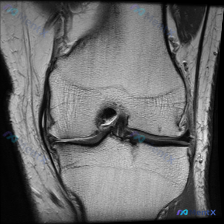

本次评估的是单张膝关节MRI T1加权序列冠状位图像,临床提出问题:影像是否存在软骨异常?

对影像的详细评估结果如下:

- 骨骼系统:股骨远端、胫骨近端骨皮质连续,无骨折,骨髓信号正常,无局灶低信号,无骨质破坏、囊变或骨赘形成

- 关节软骨:股骨髁和胫骨平台软骨表面光滑、轮廓连续、厚度均匀,无局灶性变薄或剥脱

- 半月板:内外侧半月板均为均匀低信号,轮廓完整,无异常高信号

- 韧带肌腱:交叉韧带、侧副韧带走行连续,信号均匀,无异常增高或中断

- 关节腔与软组织:关节间隙无异常狭窄,无明显积液,周围软组织结构清晰,无肿块或水肿

初步阅片结论:本次评估的单张T1冠状位图像未见明确病理学改变,所有结构均为正常信号和形态,未发现明确的创伤、退变或占位性病变。